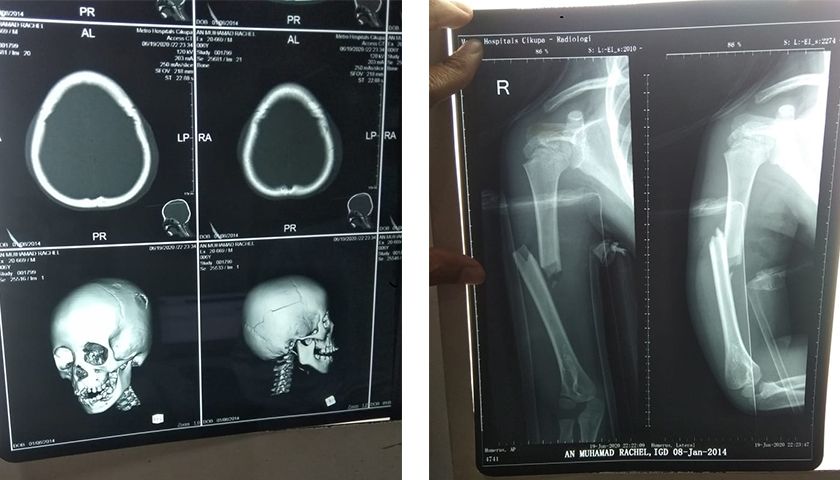

Rachel mengalami cedera di kepala dan hidung, kepala, wajah dan badannya lecet, juga tangan kanan bocah ini patah. Karena kondisinya kian parah, Rachel dirujuk ke RS Fatmawati Jakarta dan harus dilakukan operasi se-segera mungkin.